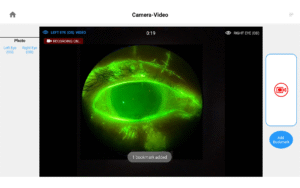

Pushing ahead, our imaging system includes our new, patent-pending Halo background light. Working with native slit lamp illumination, Halo delivers unparalleled clarity of the ocular adnexa. You’ll uncover details of the meibomian glands, acinar spaces, conjunctiva, lid margins, and lashes like never before.